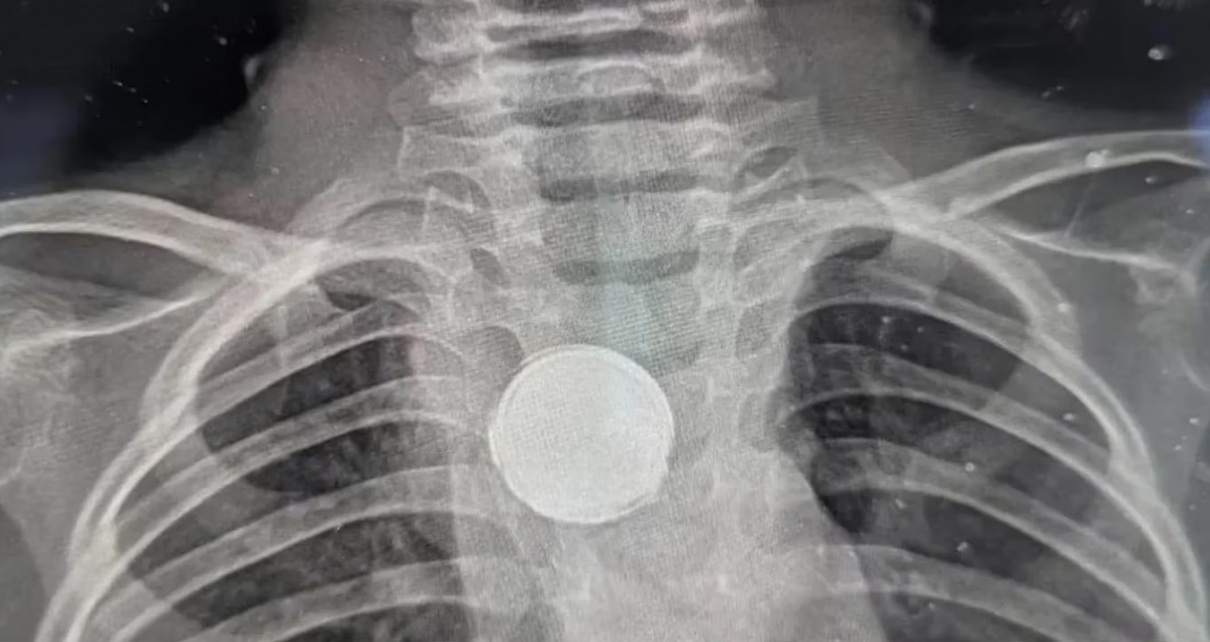

A través de una radiografía de tórax, el nuevo médico que atendió al nene encontró lo que le sucedía. “Les vi poner mirada extraña”, recordó la mamá de Luke y, al ver las imágenes, comenzaron a preguntar si existía la posibilidad que el se haya tragado una moneda o un botón.

De inmediato, lo trasladaron de urgencia a un hospital para determinar de qué se trataba el objeto que veían en los estudios. Según explicó la mamá, los profesionales decían: “No hay forma de que sea una pila porque comienzan a corroerse en tan solo dos horas”

En esta misma línea, Erica la mamá señaló: “Dijeron que tenía algo plateado en el pecho, pero que sería peligroso sacar ese objeto sin una cirugía completa”. De esta manera, se llevó adelante la intervención quirúrgica correspondiente y encontraron que la pila estaba envuelta en una cinta aislante, lo que permitió que no se degrade y le salvó la vida al menor de edad.